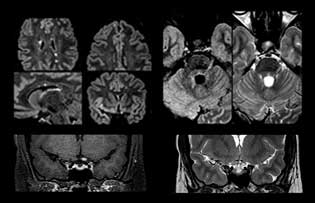

Wenn ein Verdacht auf multiple Sklerose (MS) besteht, muss das Klinikteam schnell zu einer Diagnose kommen, damit die Behandlung so bald wie möglich beginnen kann. „Eine Schwierigkeit bei der Bildgebung ist, dass MS-Läsionen im Gehirn und in der Wirbelsäule sehr klein sein können“, erläutert Dr. Savatovsky. „Wir benötigen eine präzise Bildgebung, um exakt zu bestimmen, wo sich die Läsion befindet, das heisst, wir brauchen hochwertige Bilder in sehr hoher Auflösung, vorzugsweise in 3D[1]. Wir müssen uns sicher sein, ob eine hohe T2-Signalintensität auf MS hinweist oder lediglich aspezifisch ist. Ausserdem wünschen wir uns eine sehr gute Visualisierung von aktiven Läsionen.“

„Ingenia 3.0T liefert uns eine sehr gute Bildqualität mit hohem Signal-Rausch-Verhältnis, auch wenn wir die Auflösung ausreizen. Bei FLAIR-Bildern haben wir zum Beispiel eine isotrope Auflösung von 0,9 mm. Ingenia ermöglicht uns die Nutzung von 3D-T1-TSE mit BrainView, was eine bessere Empfindlichkeit als die 2D-Spinecho-Bildgebung[2] und die 3D-Gradientenecho-Bildgebung aufweist. Ingenia liefert auch hoch reproduzierbare Untersuchungen, was bei der MS-Bildgebung wichtig ist, damit Folgeuntersuchungen zu verschiedenen Zeitpunkten auf dieselbe Weise durchgeführt werden.“

MS-Bildgebung im Gehirn

Für die MS-Bildgebung im Gehirn nutzt Dr. Savatovsky 3D-FLAIR als Basissequenz, um die Läsionen darzustellen sowie die jeweilige Situation und die Läsionsbelastung zu beurteilen. „Wir zählen die Läsionen an jeder Stelle, um zu bestimmen, ob die Kriterien der Erkrankung erfüllt sind. Dafür wird eine T2-gewichtete Sequenz verwendet, weil unsere Neurologen diese gewohnt sind. Wir vergleichen die Läsionsbelastung unter FLAIR mit einer 3D-T1-Postkontrastsequenz, damit wir feststellen können, ob die Läsionen alt oder neu sind. In der Regel verabreichen wir das Kontrastmittel vor der Aufnahme des Patienten in das System, weil sich dadurch die Untersuchungsdauer verkürzt und die Visualisierung aktiver Läsionen möglich wird, die im Allgemeinen nach mehreren Minuten deutlicher dargestellt werden. Wenn sich eine differenzielle Diagnose als schwierig herausstellt, nutzen wir weitere Sequenzen wie die Suszeptibilitätsbildgebung, da einige fokale MS-Läsionen in der Mitte eine kleine Ader aufweisen[3].“